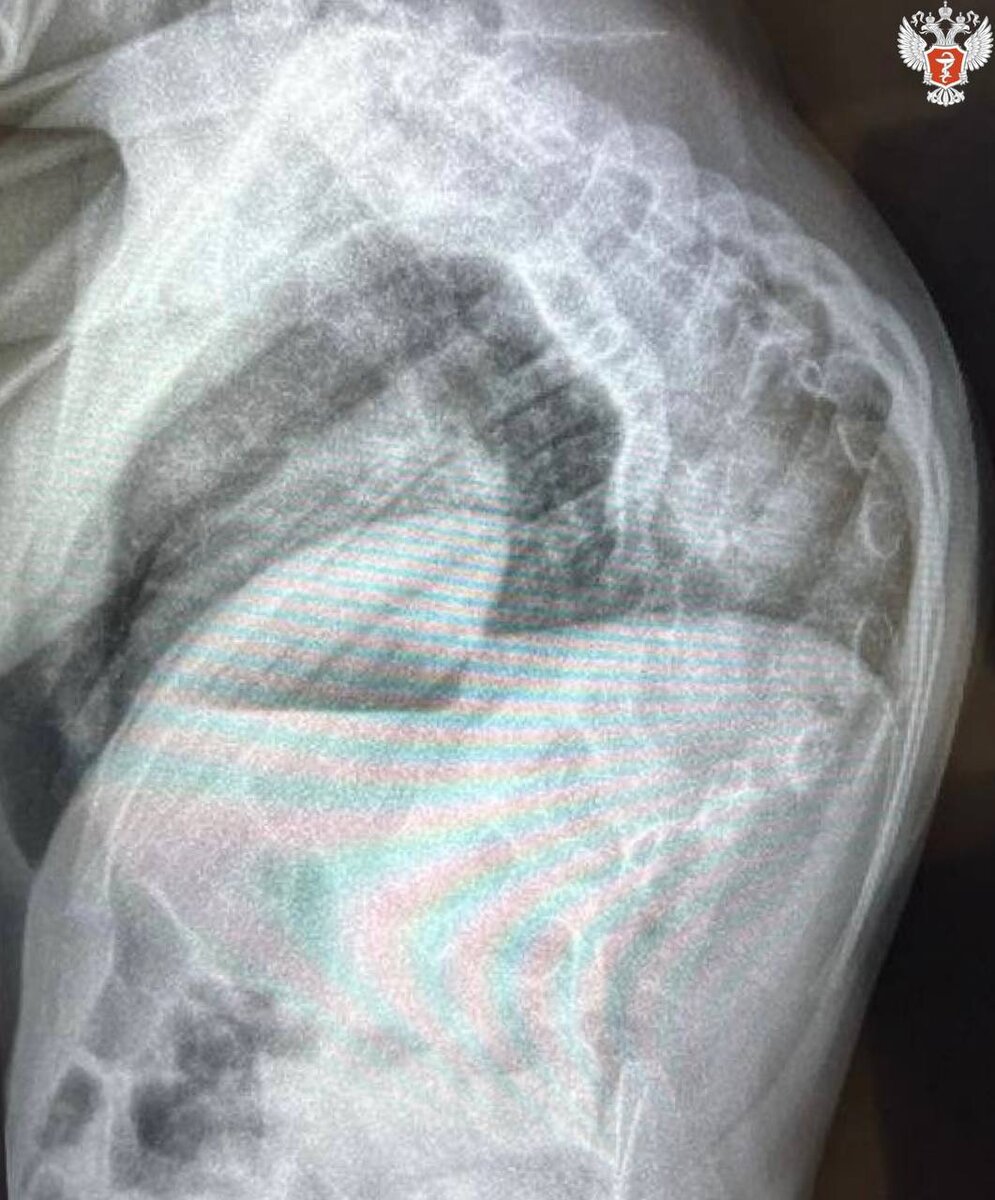

Операцию четырёхлетней жительнице Астрахани Айлане с тяжёлой формой врождённого сколиоза провели в НМИЦ детской травматологии и ортопедии им. Г. И. Турнера Минздрава России.

«В ходе операции, которая длилась три с половиной часа, нам удалось разобщить сросшиеся между собой рёбра грудной клетки, исправить врождённую деформацию позвоночника и грудной клетки при помощи индивидуальной титановой рёберно-позвоночной металлоконструкции», - сообщил Сергей Виссарионов.

В возрасте шести-семи лет рёберно-позвоночную конструкцию можно будет удалить и выполнить полноценную коррекцию врождённого искривления позвоночника при помощи спинальной системы.

Подобные операции являются новаторскими не только для центра, но и для отечественного здравоохранения. Предложенная хирургическая методика лечения и разработанная индивидуальная отечественная металлоконструкция не имеет мировых аналогов.